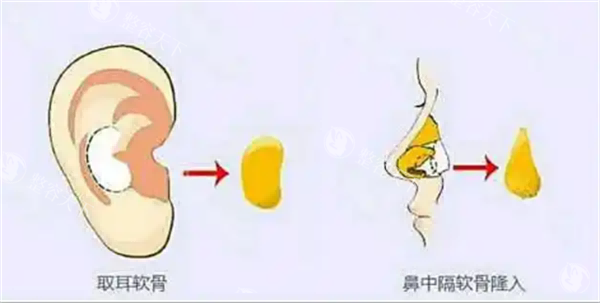

半肋软骨技术的核心优势在于“材料源于自身,塑形更贴合原生条件”。取用肋软骨中的柔性部分雕刻鼻尖支架,既能避免假体的异物感,又能精细控制鼻尖旋转度、延长鼻小柱。

仿生支架雕刻:肋软骨需保留天然弧度,模拟原生鼻中隔的力学结构;

材料处理经验:肋软骨离体后需在生理盐水中浸泡塑形,雕刻时长精细到分钟级;

一位复诊的求美者感慨:“原先担心肋软骨取完后会留疤,没想到切口藏在乳房下皱襞,修复后根本看不出痕迹。”